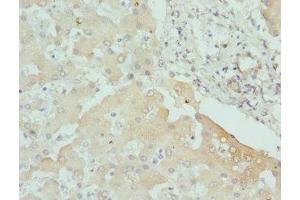

Dieser Kaninchen Polyklonal Antikörper detektiert spezifisch CPN1 in WB, IHC und ELISA. Es zeigt Reaktivität gegenüber Proben von Human.

Western Blotting (WB), Immunohistochemistry (IHC), ELISA